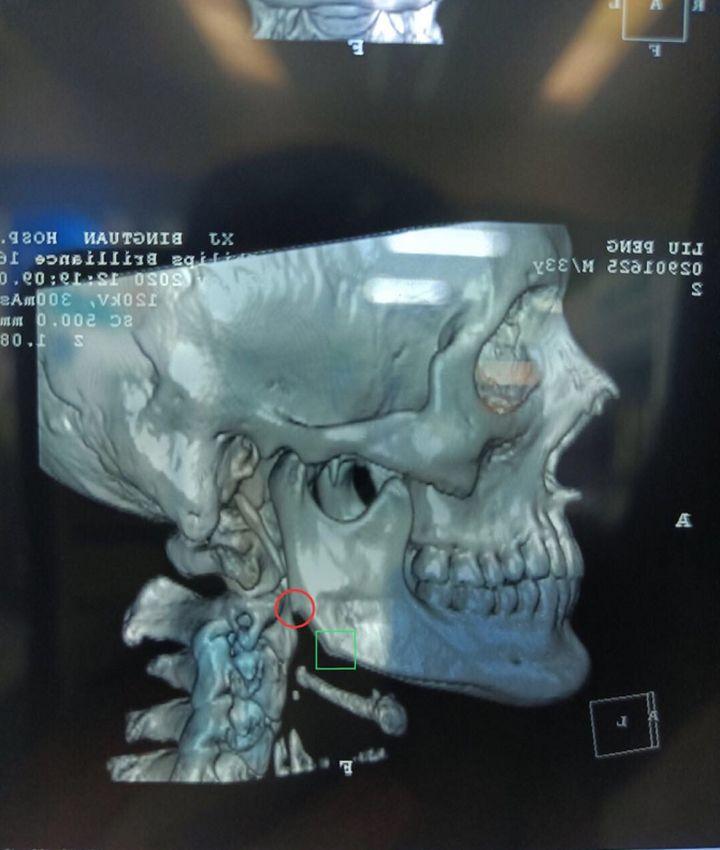

就像这种下颌角,术前是可以看出来有些宽大的。

术后的果留下二次角。

这种是医生的技术不行,可以看出来,是做了留角的,如果角度处理在一点会则会更一点,不要看到网上做的留角的失败了,就觉得不能做留角。

这种骨头类的二次修复,也是的不好做的,一般的医生都做不好,可操作的空间比较小,怕切到神经线。

一刀切的下颌角就会造成二次角,做出来的轮廓就不好看!

图片源自网上:下颌角手术

图片源自网上:下颌角

图片源自医院:下颌角术后20天

图片源自网络:下颌角术后70天